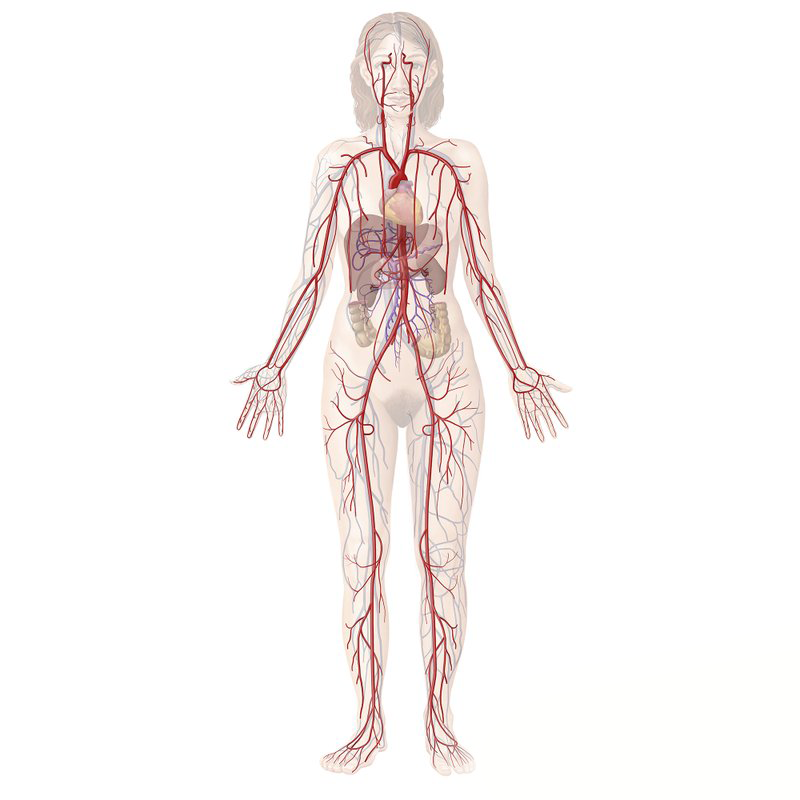

Tratamiento Circulatorio

El tratamiento circulatorio está enfocado en mejorar el flujo sanguíneo y la salud de los vasos sanguíneos, ayudando a prevenir y aliviar molestias asociadas a una circulación deficiente, como dolor, pesadez o hinchazón en las extremidades.

Incluye una valoración médica personalizada y, según cada caso, el uso de tratamientos médicos, recomendaciones de actividad física, cambios en el estilo de vida y apoyo nutricional para favorecer una mejor circulación.